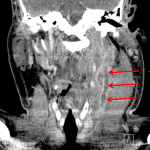

- Peripherally enhancing fluid collection deep to the left sternocleidomastoid muscle with encasement of the left internal jugular vein, which is thrombosed from the skull base to the lower neck with associated wall enhancement

- Enlargement of the overlying SCM muscle with surrounding fat stranding and thickening of the platysma muscle

- Left sided laryngeal edema and retropharyngeal edema extending from C2-C5

- Septic thrombophlebitis of the left internal jugular vein (Lemierre syndrome)

Neck abscess deep to the sternocleidomastoid muscle measuring 3 x 2.5 x 3.5 cm with encasement of the left internal jugular vein and overlying cellulitis/myositis. Thrombosis and wall enhancement of the left IJ extending from the skull base to the lower neck is consistent with septic thrombophlebitis. These findings are concerning for Lemierre syndrome. No nodules or airspace in the visualized lung apices; however consider chest CT to further evaluate for septic embolic disease.

Retropharyngeal edema without retropharyngeal abscess, which exerts mild mass effect on the pharyngeal airway.